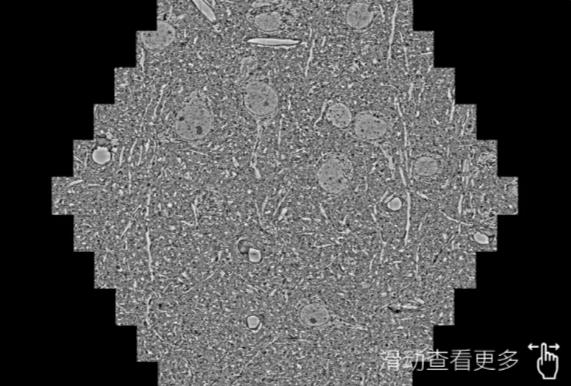

鼠脑切片。左图使用湖北蔡司湖北扫描电镜MultiSEM706对165μmx143pm面积区域成像,耗时仅需1.5秒。右图为鼠脑切片中30μm区域放大效果。样品由芝加哥大学B.Kasthuri提供。

使用蔡司高速湖北扫描电镜MultiSEM对1mm²人脑皮层组织进行高分辨成像,并对其中的各种细胞结构进行三维重构分析。左图展示了2x3mm²组织平面中锥体神经元的三维重构效果。右图显示了局部体积神经元三维重构。图像由哈佛大学chtman实验室提供,渲染图由D. Berger 制作。